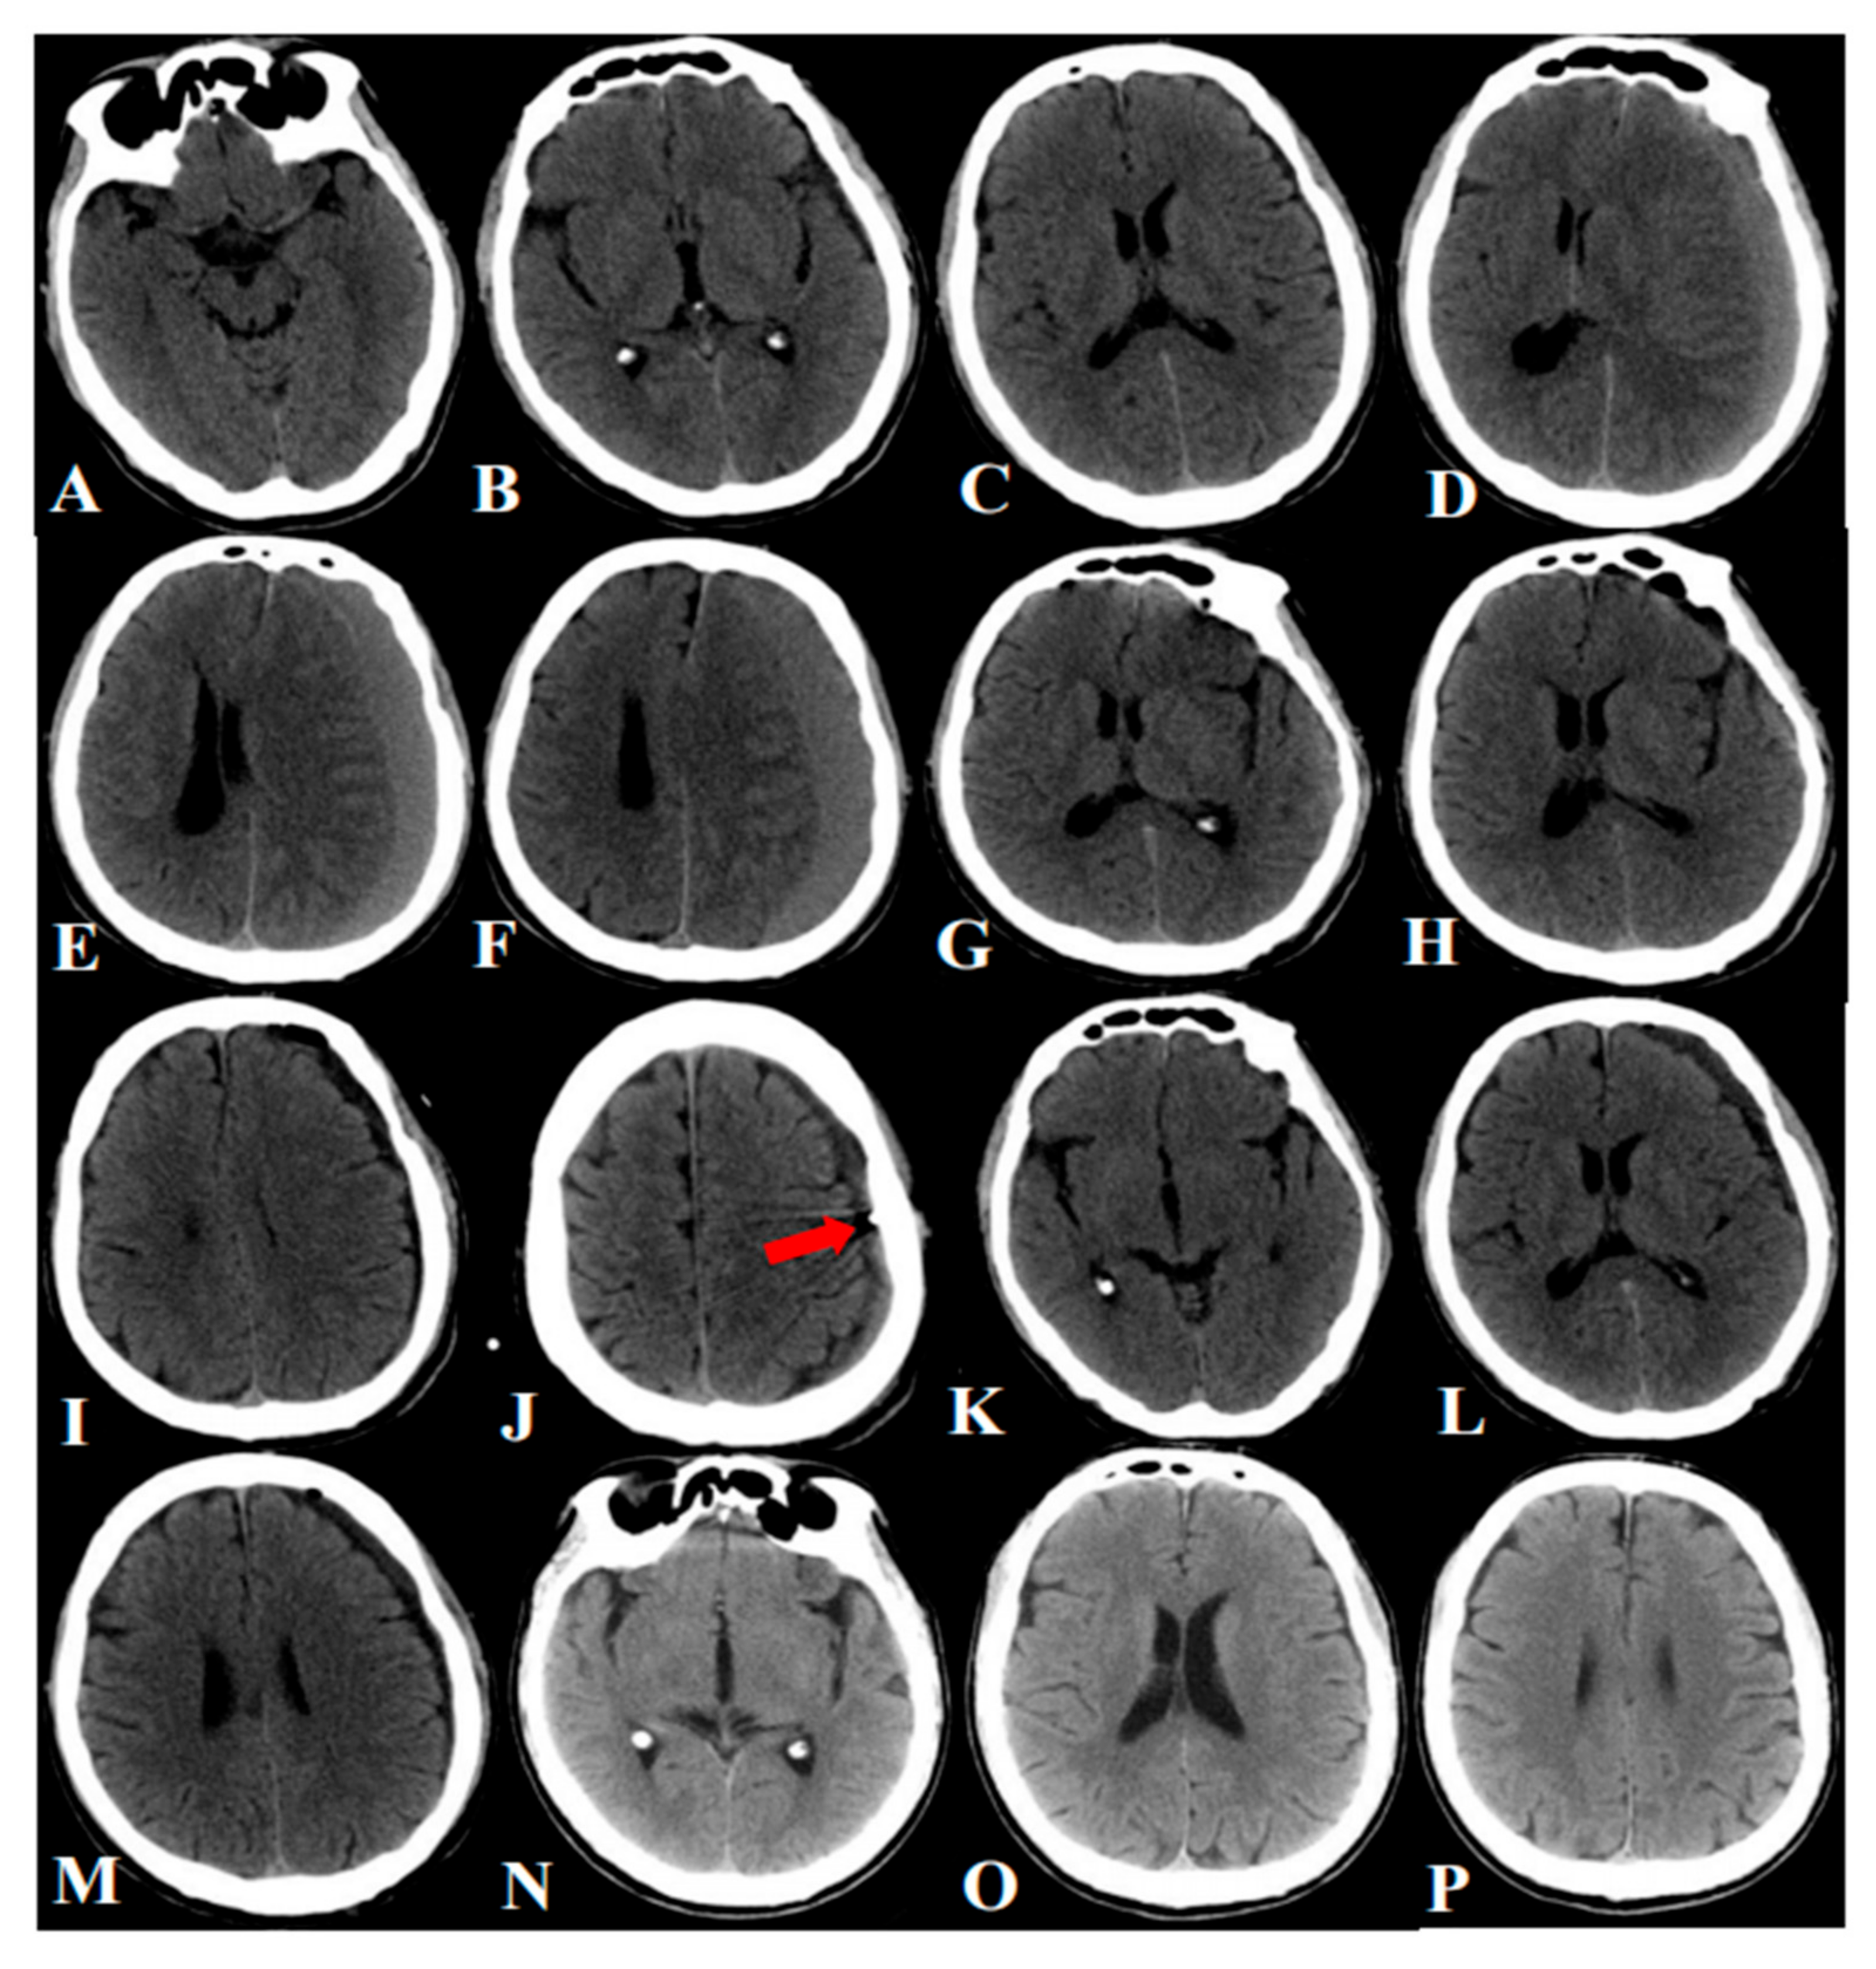

2.2. Hospitalized Flow and Surgical Procedure